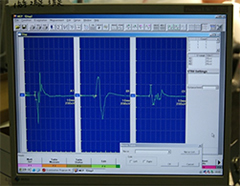

手術中MEP(運動神経)VEP(視力)モニタリングで術後の視力低下や手足の麻痺を予防する。

<手術中の脳血管撮影画像>

瘤(こぶ)は消失